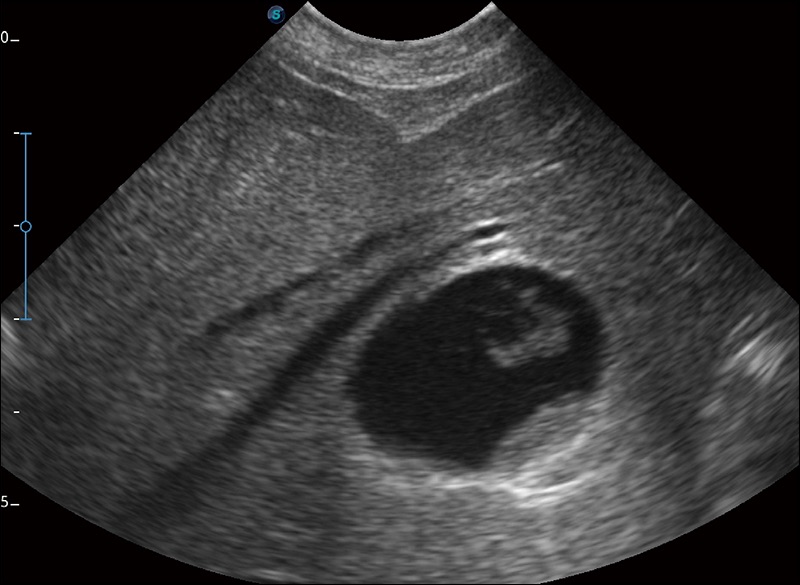

扩展成像

支持线阵和凸阵探头,一键操作即可获得更宽的图像视野

实时宽景成像

可实时观察感兴趣区域和病变位置